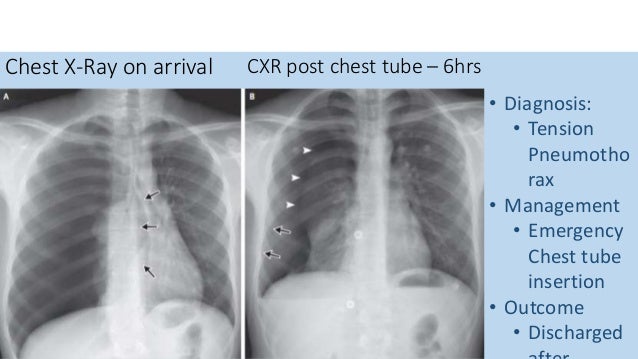

SGEM#300: The Lung is Up Where it Belongs - With or Without a Chest Tube | The Skeptics Guide to ...

SGEM#300: The Lung is Up Where it Belongs - With or Without a Chest Tube | The Skeptics Guide to ... from www.thesgem.com

Tube thoracostomy standard practice is to place a chest tube for any pneumothorax occurring during mechanical ventilation, due to the risk of positive pressure expanding the pneumothorax into a tension pneumothorax. Chest tube insertion for pneumothorax or hematothorax.this video will show you how to insert a chest tube for a pneumothoraxthis patient has multiple rib fra. How does a chest tube work for a pneumothorax? Common reasons why a chest tube is needed include: However, if the leak or pneumothorax is large, then subcutaneous emphysema or an expanding symptomatic pneumothorax is more likely. This leak may be the result of lung disease. How do you fix a pneumothorax? Treating pneumothorax in the icu:

What is the standard treatment for a pneumothorax? 6 a larger pneumothorax, or one that involves a large air leak, may need a chest tube of 24f to 28f connected to a drainage system with suction applied. Chest tube insertion for pneumothorax or hematothorax.this video will show you how to insert a chest tube for a pneumothoraxthis patient has multiple rib fra. This leak may be the result of lung disease. How long does it take to recover from a pneumothorax? More images for pneumothorax chest tube » Treating pneumothorax in the icu: Feb 01, 2001 · chest tube removal. Tube thoracostomy standard practice is to place a chest tube for any pneumothorax occurring during mechanical ventilation, due to the risk of positive pressure expanding the pneumothorax into a tension pneumothorax. Collapsed lung (pneumothorax)—this occurs when air has built up in the area around the lungs (the pleural space) from a leak in the lung. Aug 01, 2005 · keeping chest tubes on water seal is safe for most patients with an air leak and a pneumothorax. Thefirst stage requires that a chest radiograph demonstrates completeresolution of the pneumothorax and that there is no clinical evidenceof an ongoing air leak. How do you fix a pneumothorax?